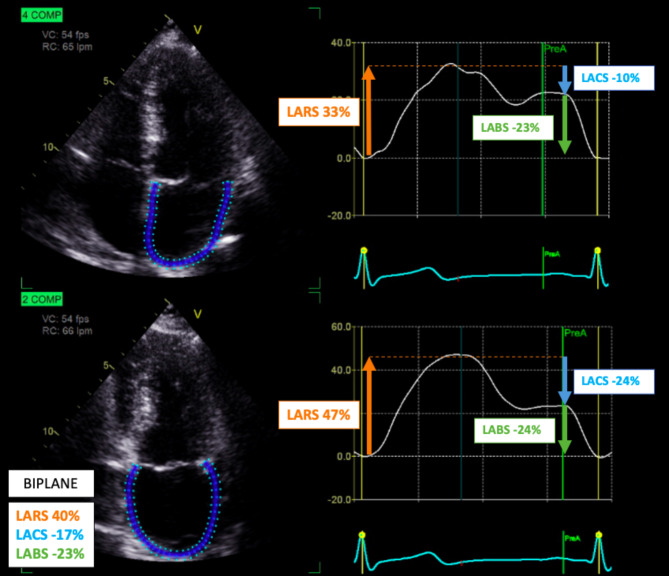

Methods: Transthoracic echocardiographic examinations in patients without CV disease were prospectively selected in two tertiary hospitals echocardiography labs for clinical purposes. LAS, maximal and minimal left atrial (LA) volumes and left atrial ejection fraction (LAEF) were measured using the two-dimensional strain analysis package provided by the EchoPAC Plugging workstation (AFI LA).

Results: A total of 196 cases were included, median age of 54 (45-62) with 85 (43%) being men. The mean left ventricular ejection fraction (LVEF) was 61% ± 5, and the median GLS was - 18% (-17 to -20). Median indexed maximum volume of left atrium (LAVI) was 27 ml/m2 (22-31), and LAEF was 64% (58-70). The mean LARS biplane was 35,1% ± 8. Notably, LARS was greater in the 2-chamber view (36,1% ± 10) compared to the 4-chamber view (34,1% ± 8 p < 0,05). The multivariate analysis of LARS revealed that sex, GLS, LAEF and e'mean are independently correlated with LARS. Multivariate analysis of LACS showed independent correlations between LACS and age, GLS, LAEF, E/A ratio and e'mean. Conversely, the multivariate analysis of LABS demonstrated significant correlations among A wave, e'mean, and left atrial stiffness index (LASI).